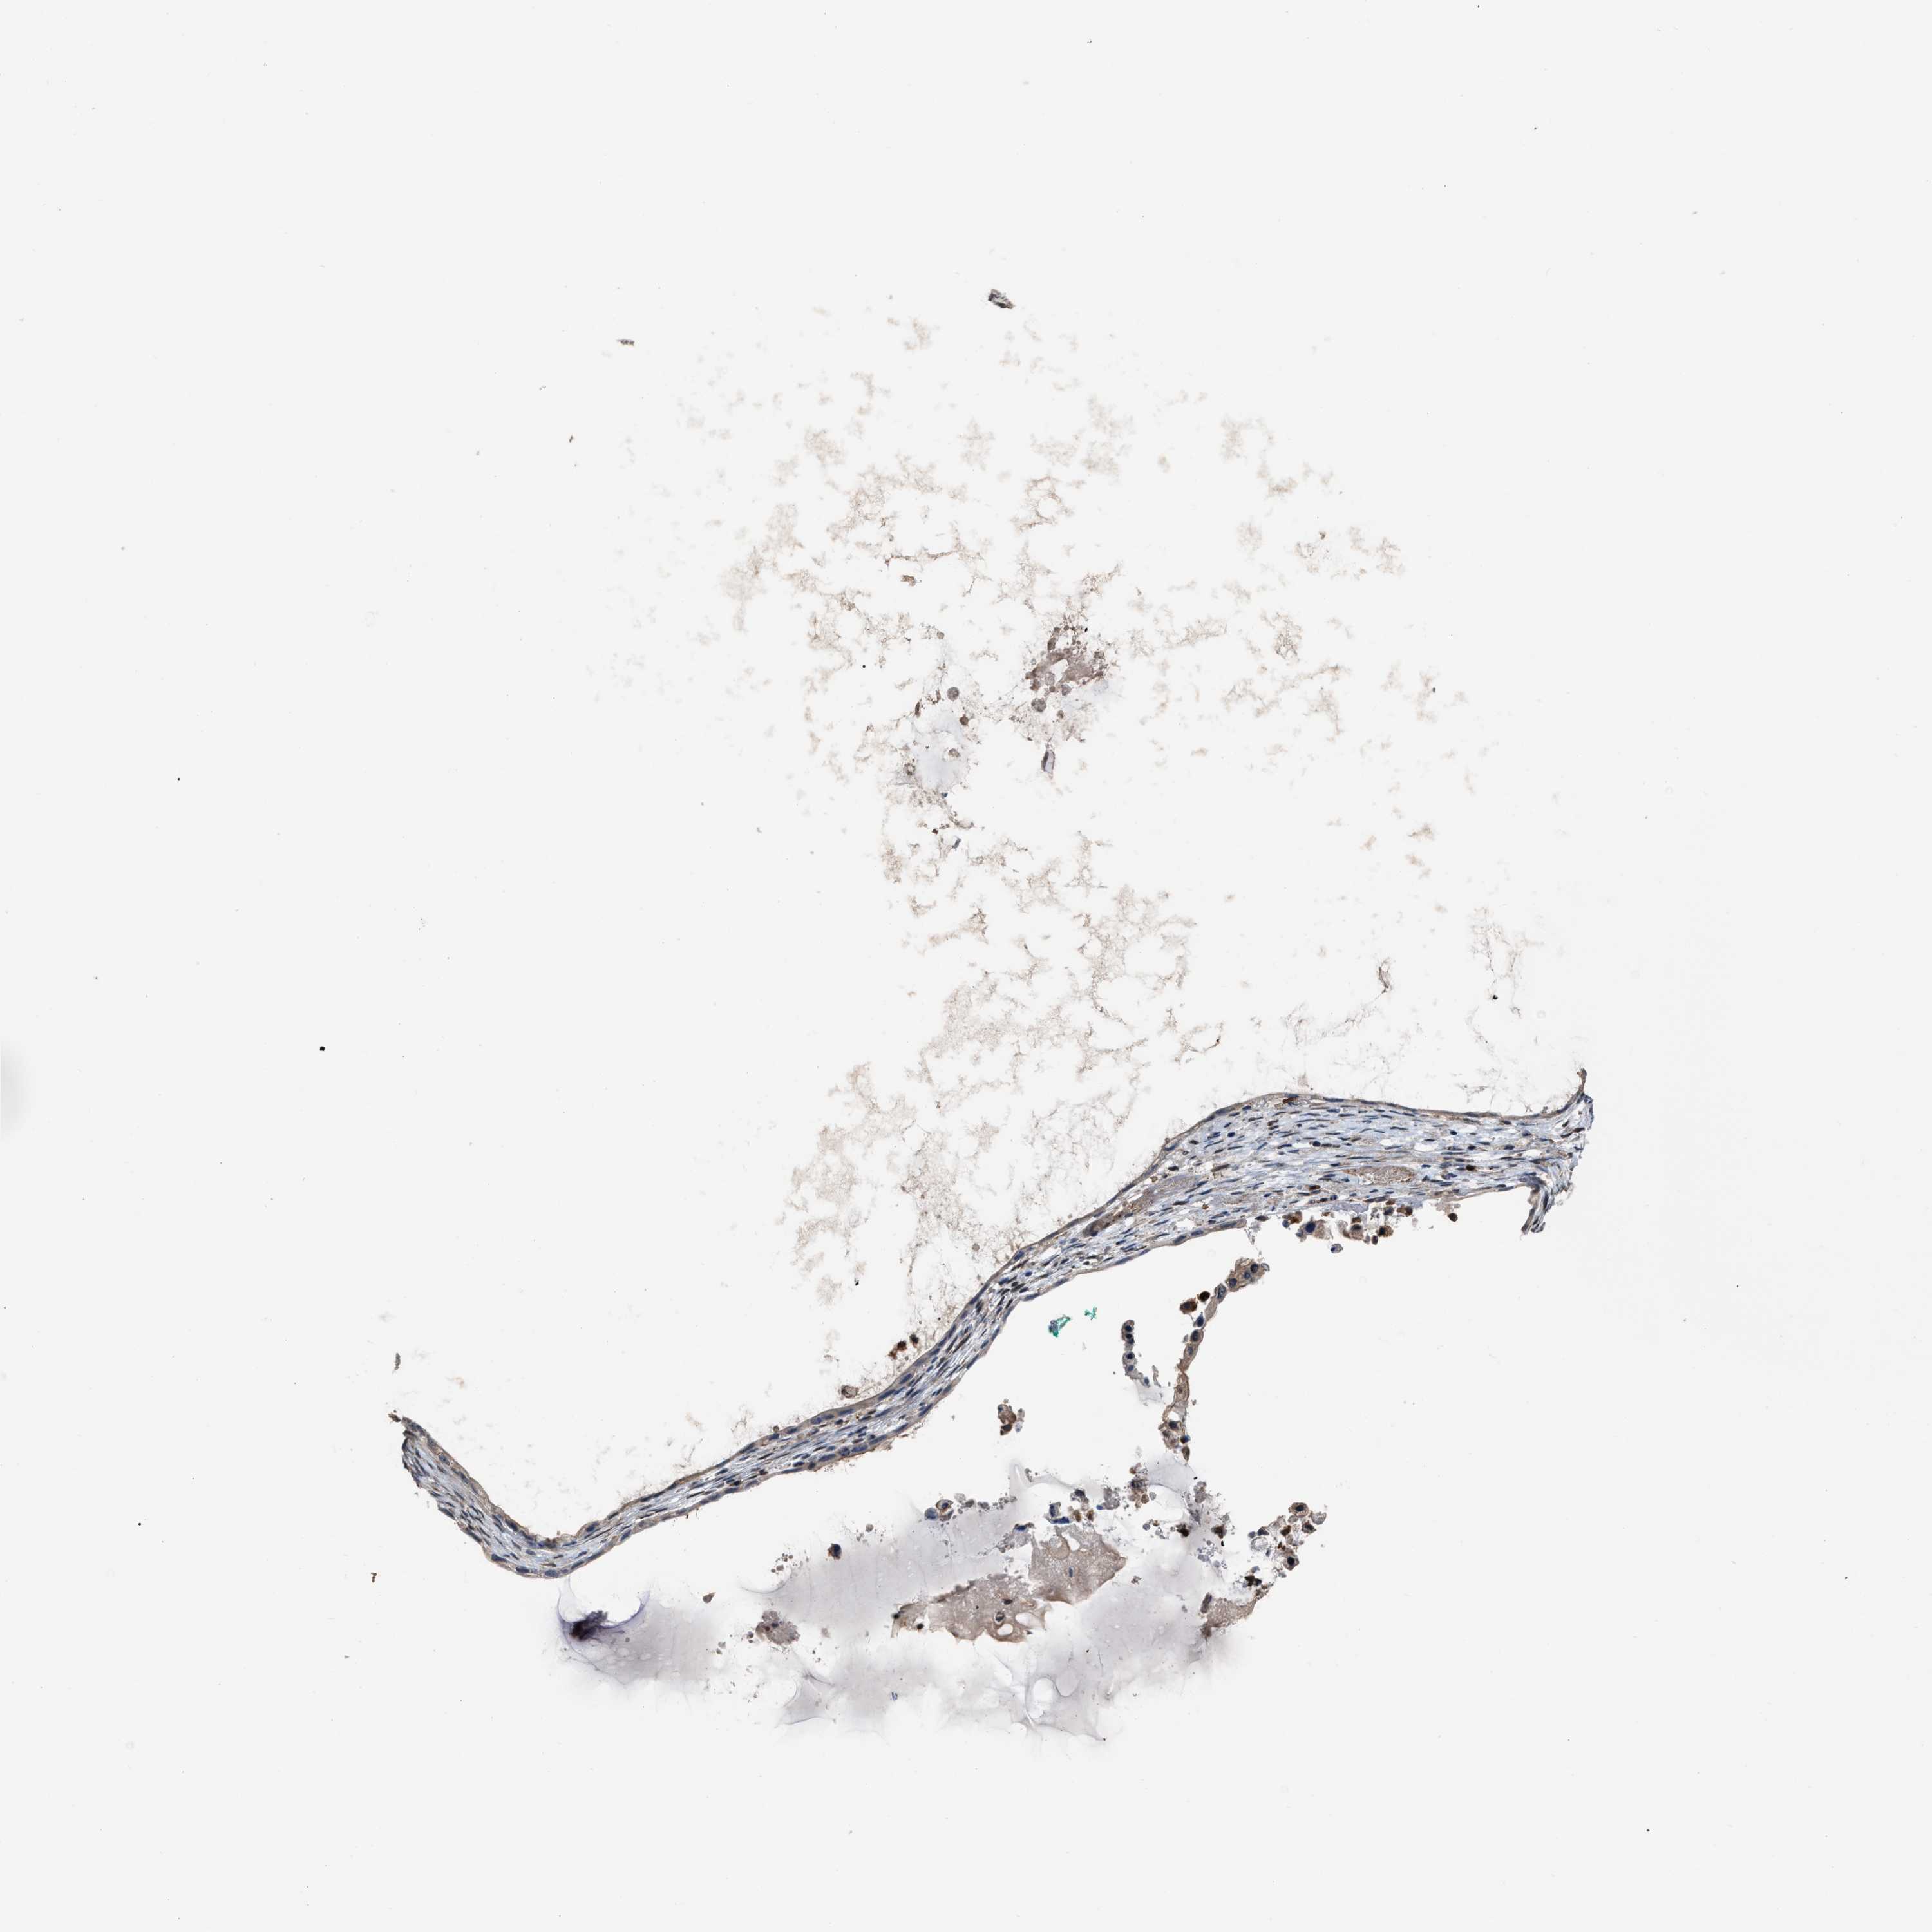

OVARIAN CANCER - Protein expressioni

A mouse-over function shows sample information and annotation data. Click on an image to view it in a full screen mode. Samples can be filtered based on level of antibody staining by selecting one or several of the following categories: high, medium, low and not detected. The assay and annotation is described here.

Note that samples used for immunohistochemistry by the Human Protein Atlas do not correspond to samples in the TCGA dataset.

Antibody stainingi

Antibody staining in the annotated cell types in the current human tissue is reported as not detected, low, medium, or high, based on conventional immunohistochemistry profiling in selected tissues. This score is based on the combination of the staining intensity and fraction of stained cells.

Each image is clickable and will lead to virtual microscopy that enables deeper exploration of all samples and also displays staining intensity scores, fraction scores and subcellular localization as well as patient and tissue information for each sample.

Antibody HPA019735

Staining

High

Medium

Low

Not detected

Intensity

Strong

Moderate

Weak

Negative

Quantity

>75%

75%-25%

<25%

None

Location

Nuclear

Cytoplasmic/membranous

Cytoplasmic/membranous,nuclear

Cystadenocarcinoma, serous, NOS

Carcinoma, endometroid

Cystadenocarcinoma, mucinous, NOS

Carcinoma, NOS